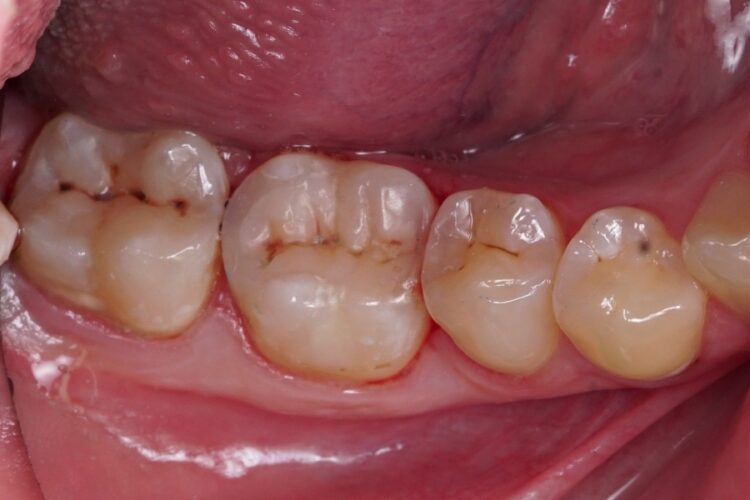

Пломбування жувальних зубів фотополімером

Пацієнт звернувся зі скаргою на постійне застрягання їжі між бічними зубами, та неприємний запах при чищенні зубною ниткою між ними. Було діагностовано неякісне прилягання старих пломб та вторинний карієс, що розвинувся під ними. Ми провели очищення зубів від старого матеріалу та каріозного ураження. Пломбування зубів проведено матеріалом ASTERIA, Tokuyama (Японія) з формуванням якісного та щільного контакту між ними.